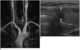

Hypovascularity